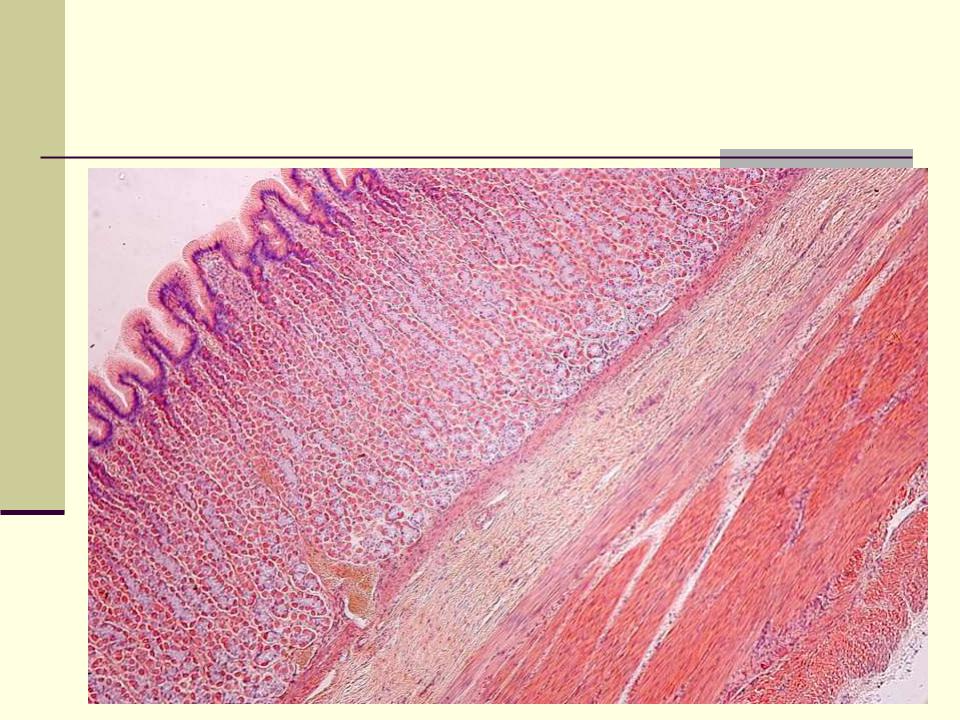

СЛИЗИСТАЯ оболочка желудка состоит из:

Эпителия

Собственной пластинки

Мышечной пластинки

Желудок (малое увеличение)

Собственная пластинка слизистой оболочки:

Образована РВСТ с большим кол-вом

кровеносных и лимфатических сосудов.

Здесь располагаются железы желудка:

собственные (фундальные)

кардиальные

пилорические.